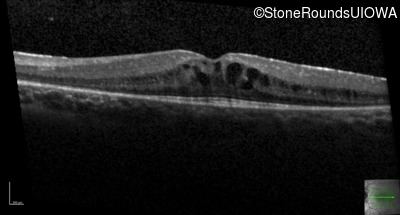

Age at visit: 7 years

OD OS

Age at visit: 7 years (Visit 2)